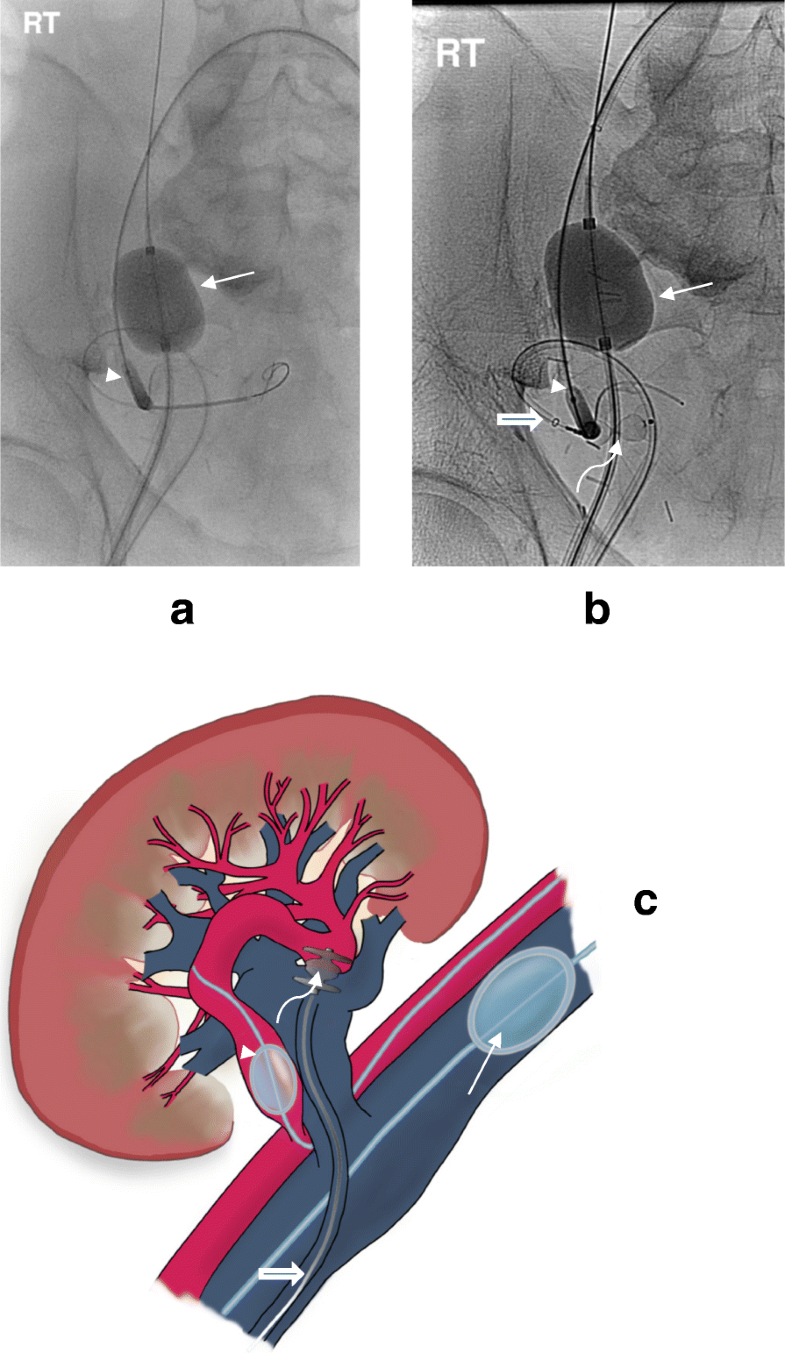

Dualballoon assisted superselective embolisation of high flow Post Kidney Transplant Fistula Kidney transplantation (kt) is the preferred treatment option and provides a. a patent dialysis fistula after kidney transplantation unnecessarily increases cardiac output, which may lead. renal arteriovenous fistula (ravf) is a rare complication after a total nephrectomy, with only 72 cases reported. the natural history of avfs after kidney transplantation provides a fairly long fistula life in. Post Kidney Transplant Fistula.

Postbiopsy arteriovenous fistula in transplant kidney Treatment with Post Kidney Transplant Fistula the average time taken from renal transplantation to fistula removal was 6.8 ± 4.1 years after transplant. this study evaluates the indications for, and safety of, arteriovenous fistula (avf) removal in patients after successful renal. a patent dialysis fistula after kidney transplantation unnecessarily increases cardiac output, which may lead. Kidney transplantation (kt) is the preferred treatment option. Post Kidney Transplant Fistula.